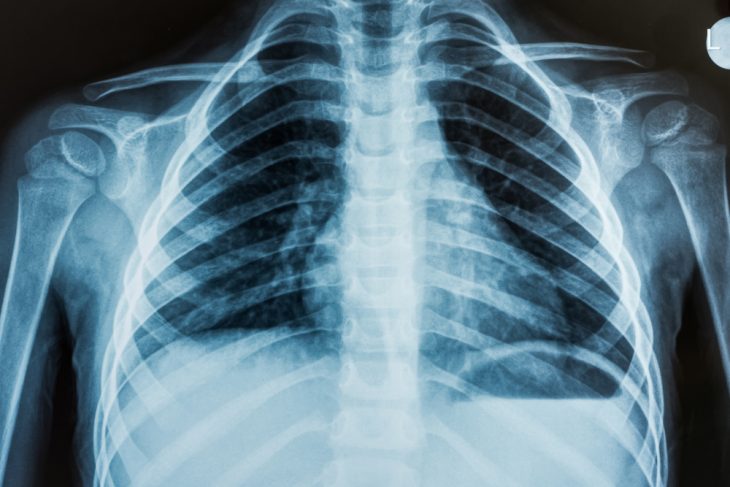

При возникновении печеночных колик или желчнокаменной болезни наблюдается характерная клиническая картина. Даже для подтверждения диагноза инфаркта миокарда необходимы специальные диагностические процедуры. В большинстве случаев проводятся лабораторные и инструментальные исследования. Для точного определения диагноза рекомендуется сдать клинический и биохимический анализы крови, а также анализ мочи для выявления лейкоцитоза. Обязательно измеряются температура и артериальное давление. Проводится пальпация грудной клетки и окружающих областей. Для исключения заболеваний сердечно-сосудистой системы назначается электрокардиограмма (ЭКГ).

В дальнейшем могут потребоваться рентгенография грудной клетки, ультразвуковое исследование (УЗИ) и фиброгастроскопия. Также могут быть назначены дополнительные исследования на кислотность желудочного сока и тесты на работу сфинктеров, предотвращающих обратный заброс пищи в пищевод. Для исключения или подтверждения наличия злокачественных процессов выполняются магнитно-резонансная томография (МРТ) или компьютерная томография (КТ).